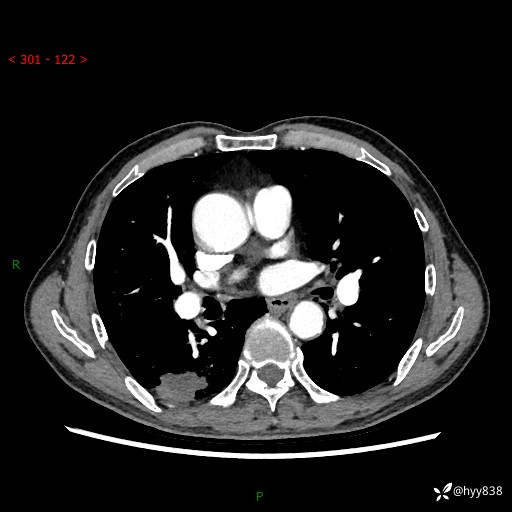

辅助检查:CT

胸部CT平扫

增强